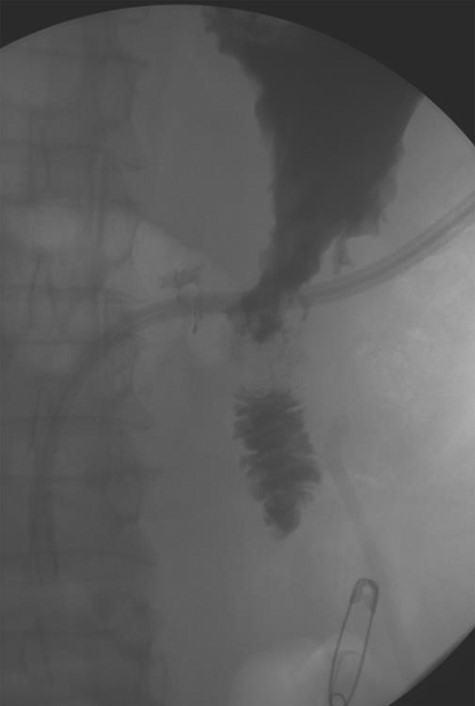

Three years later, the patient presented to the emergency department with epigastric pain as well as melena. The patient could not remember the last time he took any acid suppression medication. He had increased his intake of ibuprofen. The patient was found to have a Hgb of 6.5 g/dl. He was given 2 U of PRBC and was taken to the endoscopy suite by the gastroenterology team. The endoscopy demonstrated a posterior duodenal bulb ulcer with a metallic ring in the center (Fig. 3). At this point, the general surgery team was consulted. A computed tomography scan of his abdomen and pelvis was obtained to further guide our operative decision-making (Fig. 4).

Single axial view of subsequent computed tomography scan demonstrating scattering from GDA coil with associated area suspicious for ulcer in duodenal bulb